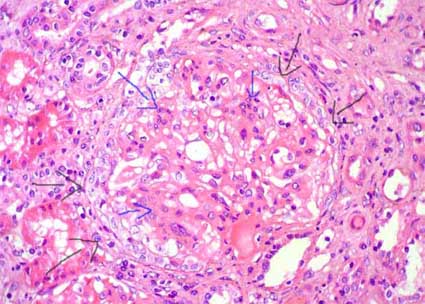

Figura 5. Mismo caso de la microfotografía anterior; observe el penacho comprimido por una semiluna epitelial circunferencial (flechas negras); hay proliferación mesangial celular y de la matriz (flechas azules). Este caso corresponde al de una mujer de 32 años con episodios de hematuria macro, en el último, previo a la bopisia, presentó además elevación de la creatinina. Las semilunas extensas en NIgA se asocian con un curso clínico más agresivo. (H&E, X400).